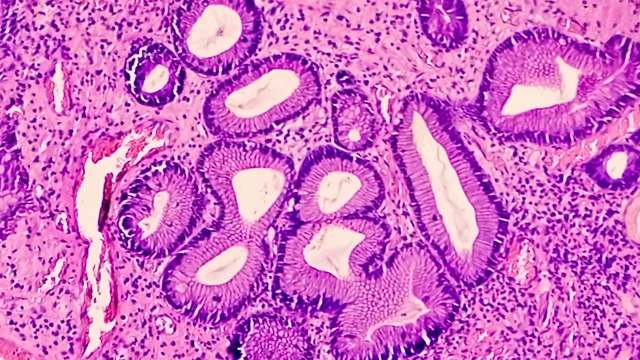

Polyp dạ dày là những khối u nhỏ phát triển từ lớp niêm mạc dạ dày, thường được phát hiện tình cờ khi nội soi tiêu hóa. Nhiều người lo lắng polyp dạ dày có phải là ung thư không? Liệu có nguy hiểm gì không?